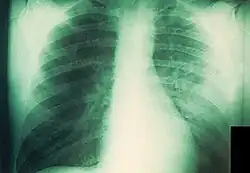

Infizierte Lunge: Streifige Zeichnungsvermehrung im mittleren Teil der linken Lunge, atypische Lungenentzündung

Die durch Tröpfcheninfektion übertragene primäre Lungenpest ist die einzige Pestform mit direktem Ansteckungsweg ohne Zwischenwirt. Nur unter besonders begünstigenden Umständen kann eine Lungenpest zur Epidemie werden und nur ein kleiner Teil der pestinfizierten Bevölkerung bekommt Lungenpest.[27] Die Ansteckung erfolgt entweder von Mensch zu Mensch, häufiger aber durch Schoßtiere. Die meisten amerikanischen Lungenpestpatienten des 21. Jahrhunderts hatten sich bei ihrer infizierten Katze angesteckt. Die Inkubationszeit wird mit 1 bis 3 Tagen angegeben. Die Lungenpest verläuft fulminanter als die Beulenpest, weil die Lymphknoten bei direkter Infektion der Lunge umgangen werden. Die Symptome der Erkrankung sind Atemnot, Husten, Blaufärbung der Lippen und schwarz-blutiger Auswurf, der extrem schmerzhaft abgehustet wird. Daraus entwickelt sich rasch ein Lungenödem mit Kreislaufversagen, welches nach zwei bis fünf Tagen zum Tod führt.